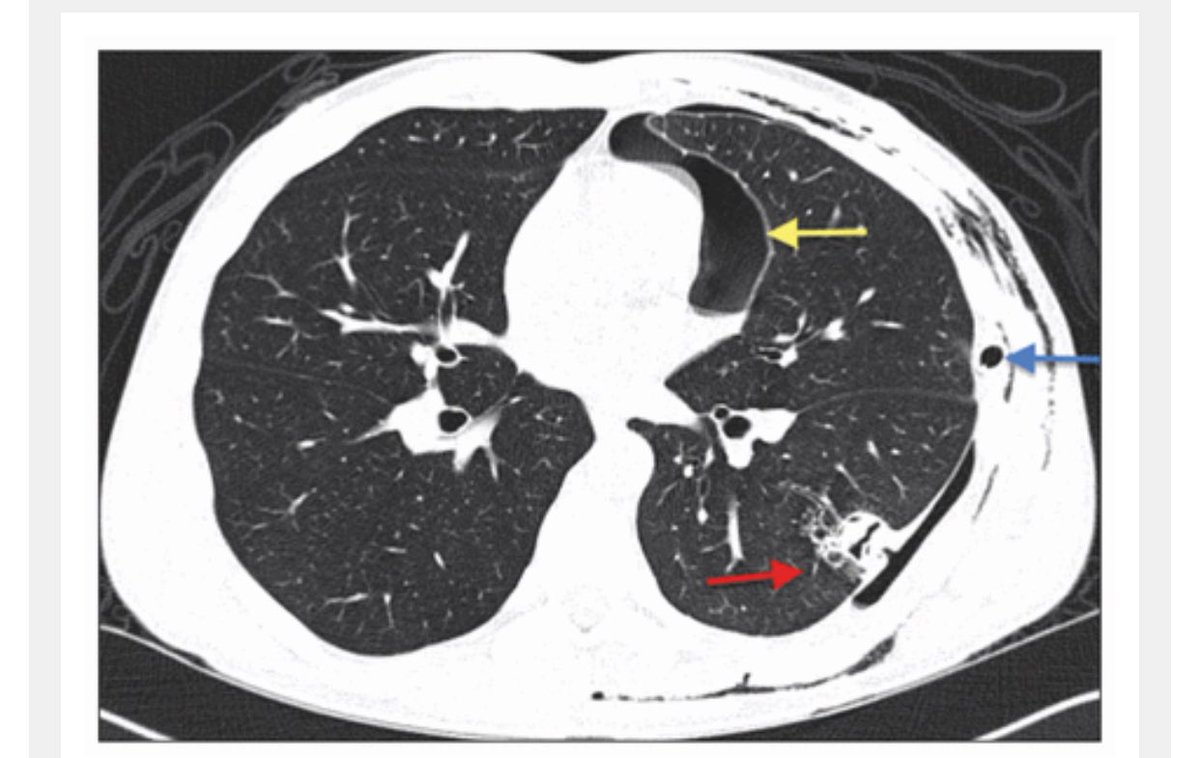

CT 30 for Aspergillus Fumigatus.~100x over the tested state limits. The hemp market enjoys ZERO testing so it’s the dumping ground of failed weed.

Fumigatus is nasty stuff for immunocompromised patients.

Aspergillosis has a 50% fatality rate.

cmaj.ca/content/187/17…Image